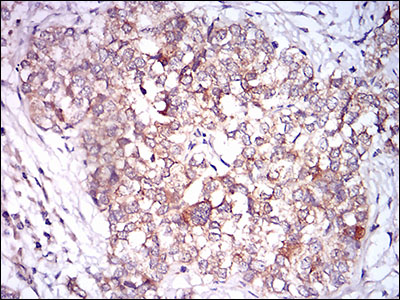

Immunohistochemical analysis of paraffin-embedded human prostate cancer tissue using anti- CaMKII gamma antibody. Counter stained with hematoxylin.

,

Immunohistochemical analysis of paraffin-embedded human bladder cancer tissue using anti- CaMKII gamma antibody. Counter stained with hematoxylin.